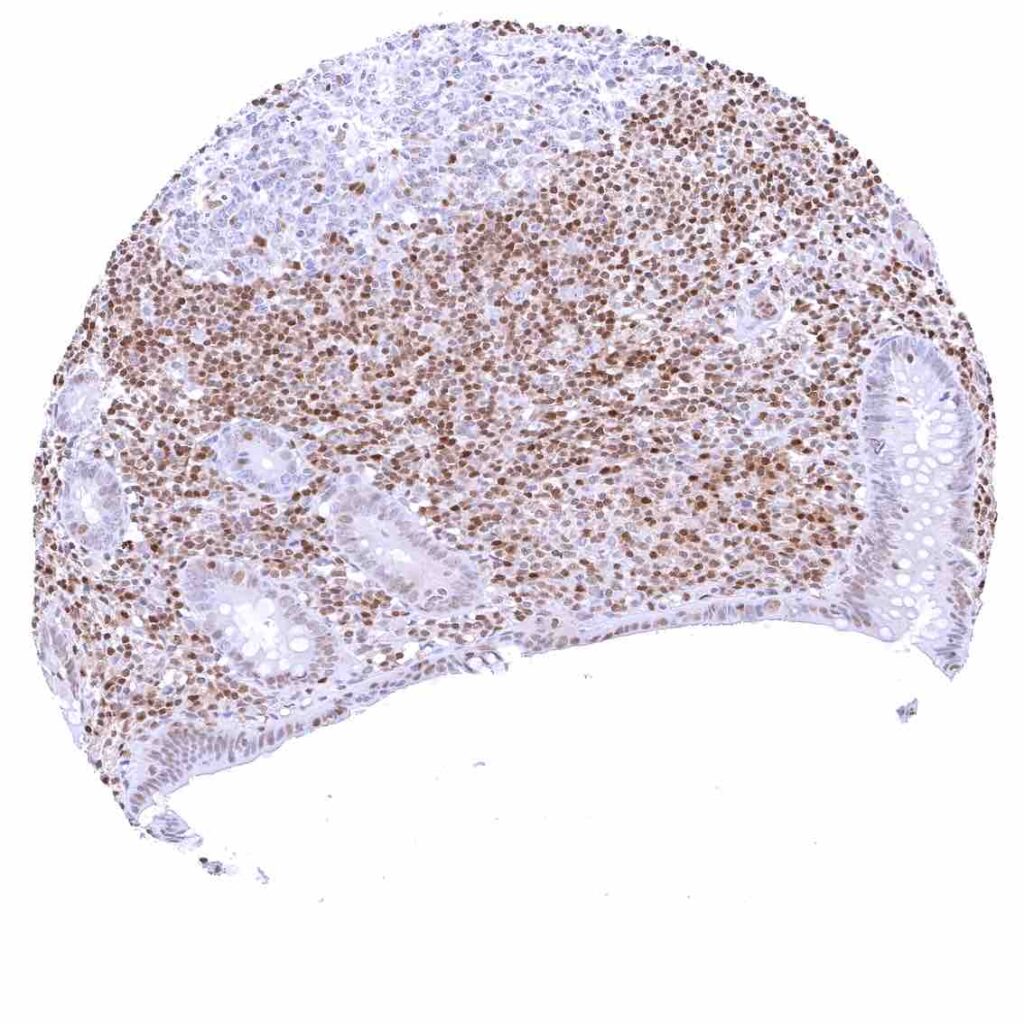

Thymus – Strong nuclear p27 staining of a large fraction of cells.